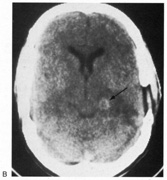

Among adults with infarction, blindness is permanent in 25%57 and residual visual field defects are common in the rest. Bioccipital CT lucencies carry a poor prognosis for recovery, but abnormal visual evoked potentials do not correlate with severity or outcome.60 Although the abnormalities on visual evoked potentials are not diagnostic, they tend to improve as vision returns.75–77 Transient cerebral blindness can last hours to days, often with full recovery (Table 2). Both ictal and post-ictal cerebral blindness are reported in children and adults.78–80 Transient cerebral blindness can occur with metabolic insults,81–83 hypertensive encephalopathy,84 hydrocephalus,85 trauma,72,86 and cortical venous thrombosis.87 Toxins are an important cause, especially chemotherapeutic agents.88–92 Cerebral blindness is associated with the iodinated contrast agents used in angiography:60,93,94 CT scans with contrast show disruption of the blood–brain barrier in the occipital lobes93,94 as early as 1 hour after angiography.95 TABLE 2. Causes of Transient Cerebral Blindness